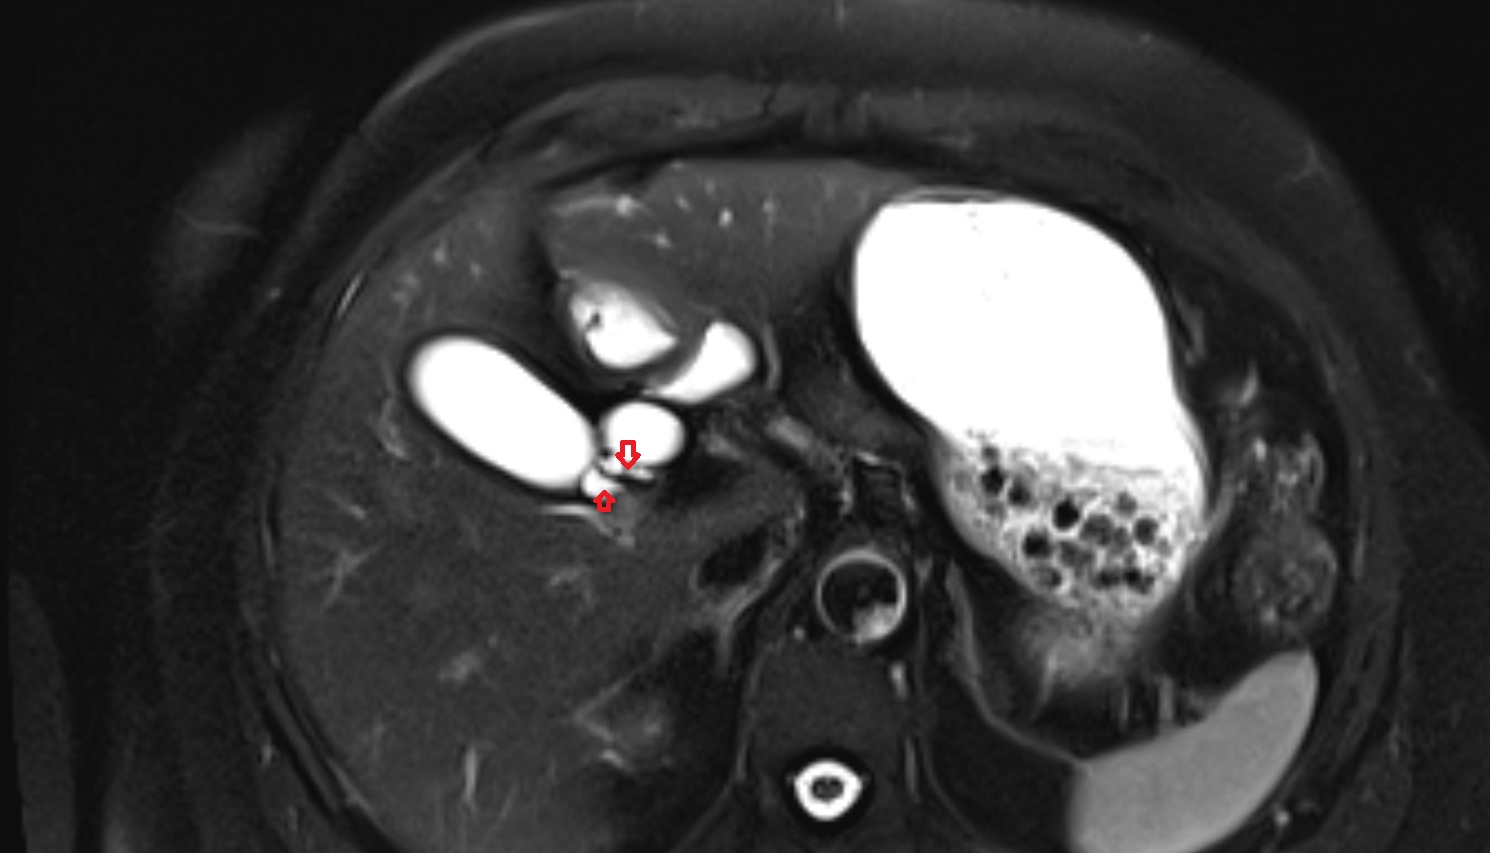

- Common bile duct